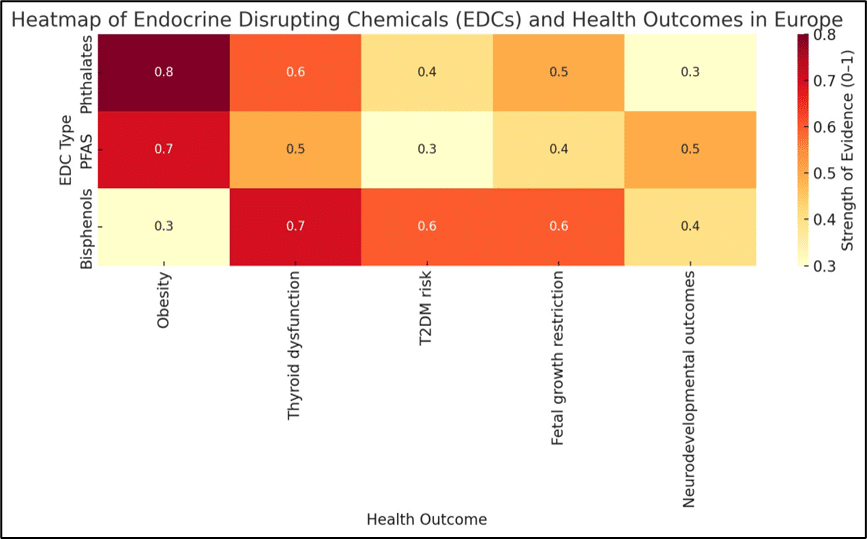

Toxicology | Aug 20, 2025

Endocrine Disrupting Chemicals and Health in Europe: A Systematic Review and Meta-Analysis

Background: Endocrine-disrupting chemicals (EDCs) are synthetic and natural compounds that interfere with hormonal regulation and are linked to obesity, diabetes,...Read More